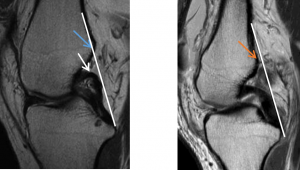

2:画一条与后交叉韧带后缘相切的线(白线),如果该切线在其远端5cm内不与股骨后侧相交,则认为PCL线为正;如图1所示,前叉连续性异常时,后交叉切斜明显股骨后侧相交(蓝色箭头位置),图2则会有一定距离(橘色箭头位置)。